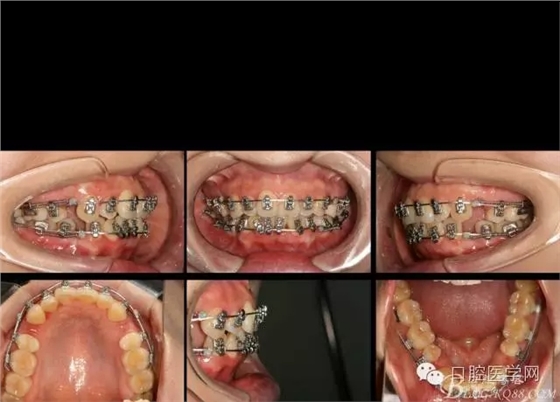

2016.6.7 第二次復(fù)診效果 上頜繼續(xù),只是將弓絲末端變長的弓絲剪斷重新回彎,其他沒有做任何處理。下頜將右側(cè)的拉簧拆掉,在右下1與3之間推簧,調(diào)整中線,其余沒動。

矯正到目前,矯正開始三個月四天,矯正比較平穩(wěn),拔牙間隙關(guān)閉接近三分之二。矯正效果明顯。每次復(fù)診處理簡潔,椅旁時間幾分鐘。大大減少醫(yī)生工作壓力,矯正療程大大縮短,是個很好的技術(shù)。

如果,矯正再輔助種植支抗,穩(wěn)定主弓絲平面以及轉(zhuǎn)移牽引力,矯正將更加平順穩(wěn)定。